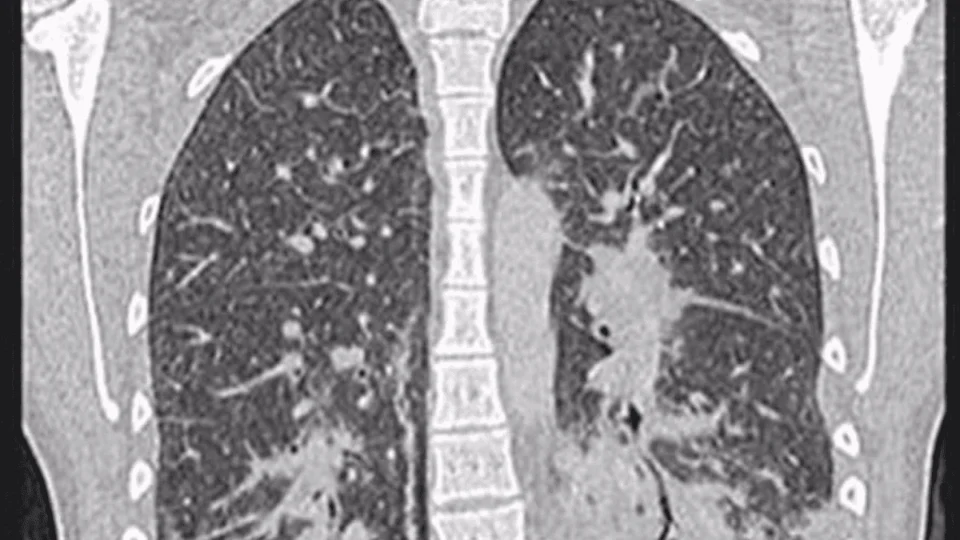

A bronquiolite obliterante ficou conhecida nos Estados Unidos como “Popcorn Lung” após trabalhadores de uma fábrica de pipoca desenvolverem a doença ao inalar uma substância chamada diacetil.

Esse composto químico, responsável por conferir sabor artificial de manteiga à pipoca de micro-ondas, provoca inflamações severas nos pulmões quando inalado com frequência.

Embora o diacetil não seja o único fator, especialistas alertam para os riscos do uso contínuo de cigarros eletrônicos, já que muitos líquidos aromatizantes (juices) utilizados nesses dispositivos contêm elementos nocivos como nicotina líquida e tetrahidrocanabinol (THC), substâncias ligadas aos casos de EVALI (Lesão Pulmonar Associada ao Uso de Produtos de Vaping ou Cigarros Eletrônicos).